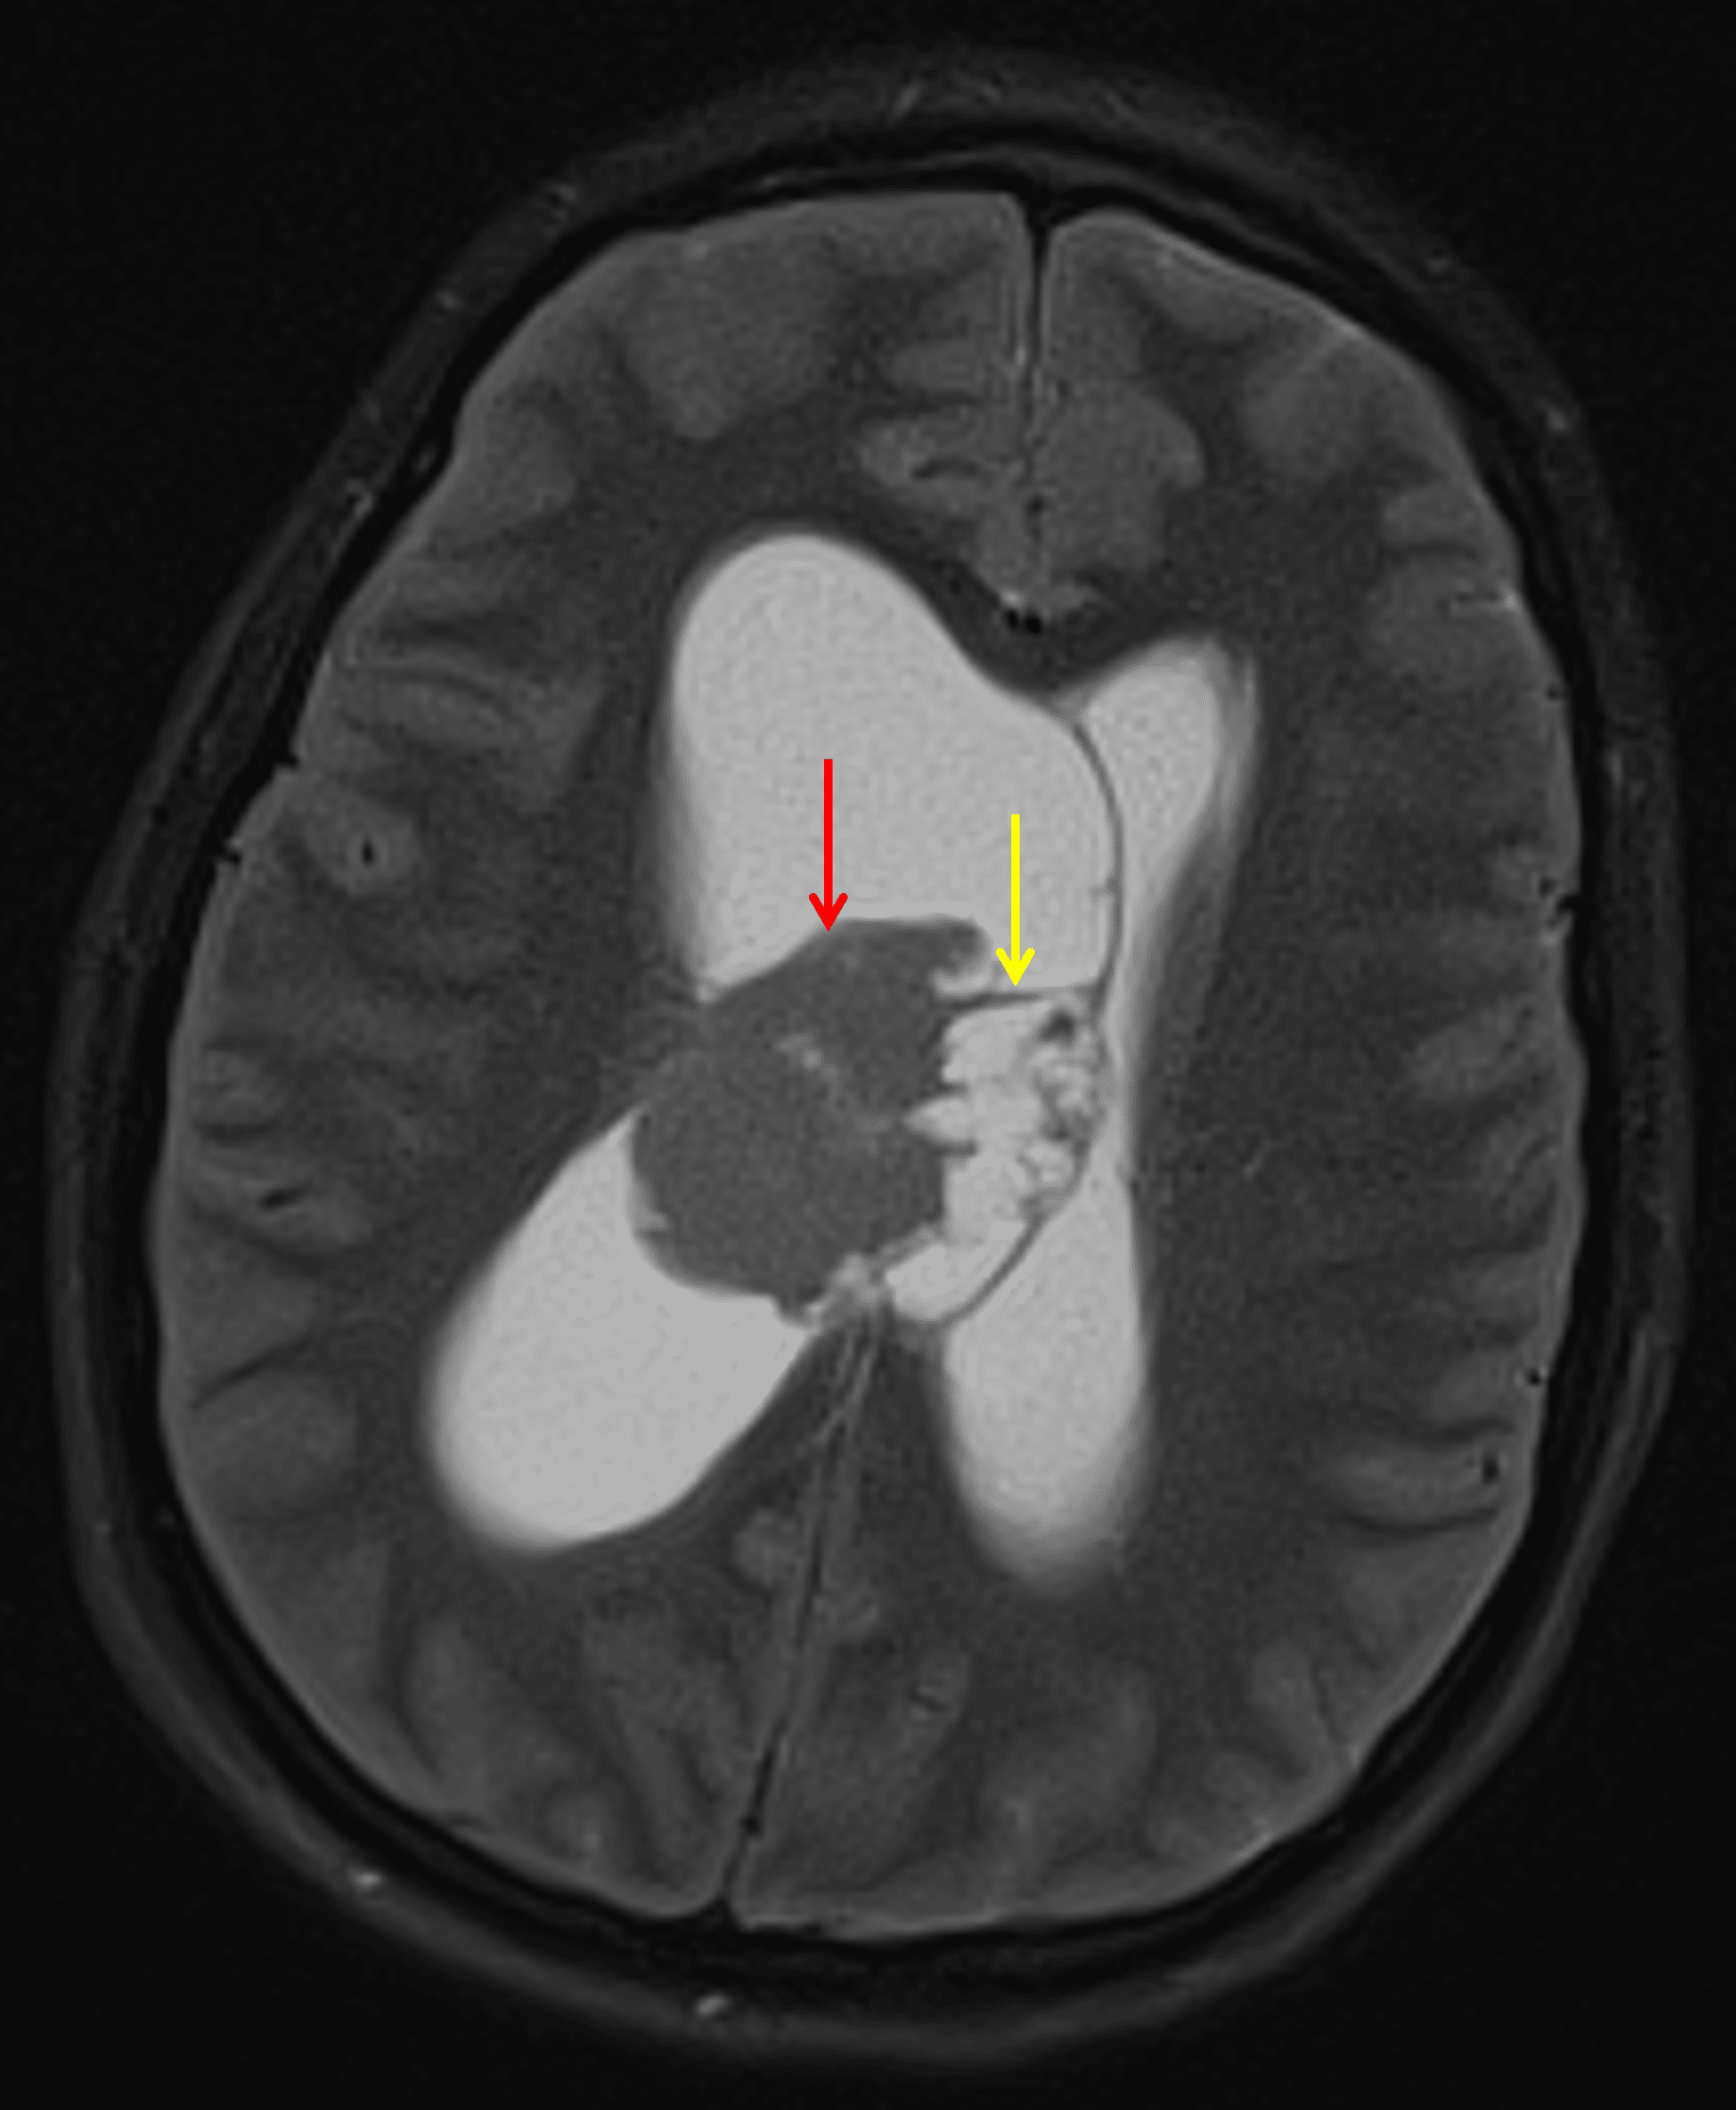

• Heterogeneous mass in the body of the right lateral ventricle measuring 3.8 x 3.4 x 3.8 cm with a solid component laterally and multiple cystic components medially, broadly contacting the septum pellucidum

Mass in the body of the right lateral ventricle with a solid component laterally (red arrow) and a cystic component medially (yellow arrow).